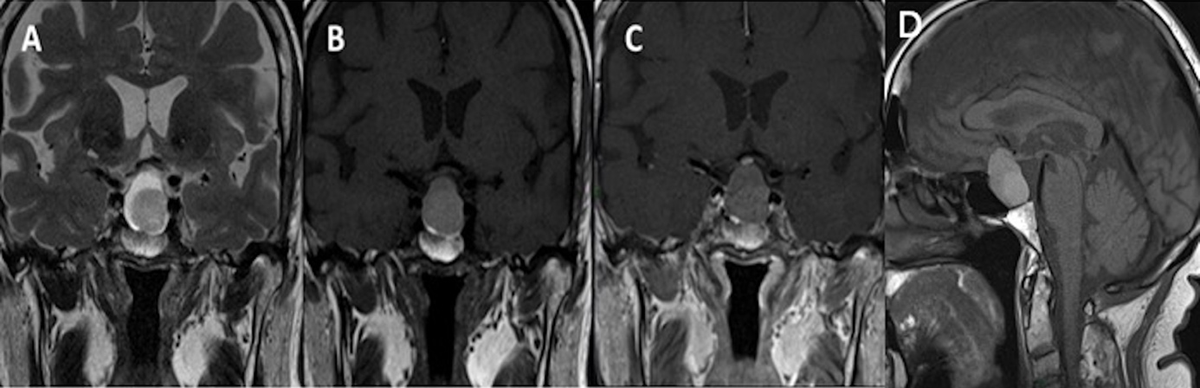

Figure 3

Intrasellar lesion in a 22-year-old female patient with a hypointense component on coronal T2WI (A), which is hyperintense on coronal (B) and sagittal (D) T1WI, and without enhancement on coronal contrast-enhanced substracted T1WI (C) diagnosed as Rathke’s cleft cyst pathologically.